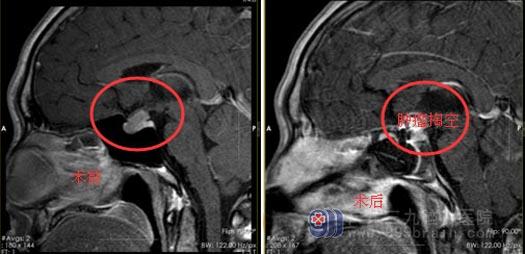

直到一个多月前,他睾丸疼痛到当地医院就诊,彩超提示“右侧睾丸鞘膜腔小结石”,催乳素>200.00ng/ml(正常育龄妇女泌乳素为5~25ng/ml),医生立马警觉地建议他脑部影像检查,头颅MR提示“鞍内-鞍上实性肿物,垂体巨腺瘤可能性大”。

经家属同意后,小陈接受了“行内镜经鼻蝶鞍区垂体大腺瘤切除术+颅底重建术”,手术顺利,成功切除肿瘤。目前已顺利出院,困扰他的问题已经解决,小陈脸上又重新挂上灿烂的笑容。